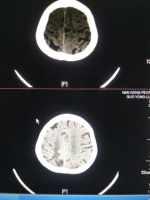

右頂葉軟化灶腦萎縮一例 關(guān)鍵疾?。?a href="http://m.akellydesign.com/tags/so/腦血栓形成-4-1.html" target="_blank">腦血栓形成高血壓3級(jí)腦出血后遺癥腦萎縮 現(xiàn)病史【一般資料】 女性,73歲, 【主訴】女性,73歲頭暈伴左側(cè)肢體無力1天 【現(xiàn)病史】患者緣于入院前1天,站起時(shí)出現(xiàn)頭暈,暈暈沉沉,休息后可緩解,伴左側(cè)肢體無力,可抬舉及站立,持物費(fèi)力,精細(xì)動(dòng)作差,無頭痛,無惡心、嘔吐,無飲水無嗆咳,無咳嗽、咳痰,無腹痛、腹瀉。為求診治而來我院就診,頭顱CT:右頂葉軟化灶腦萎縮。遂以“腦血栓形成”收入院。自發(fā)病以來,患者神志清,精神可,食欲可,睡眠一般,大小便如常。 【既往史】既往腦出血病史1年半,遺留左側(cè)肢體活動(dòng)欠靈活;高血壓病史1年半,最高220/100m...